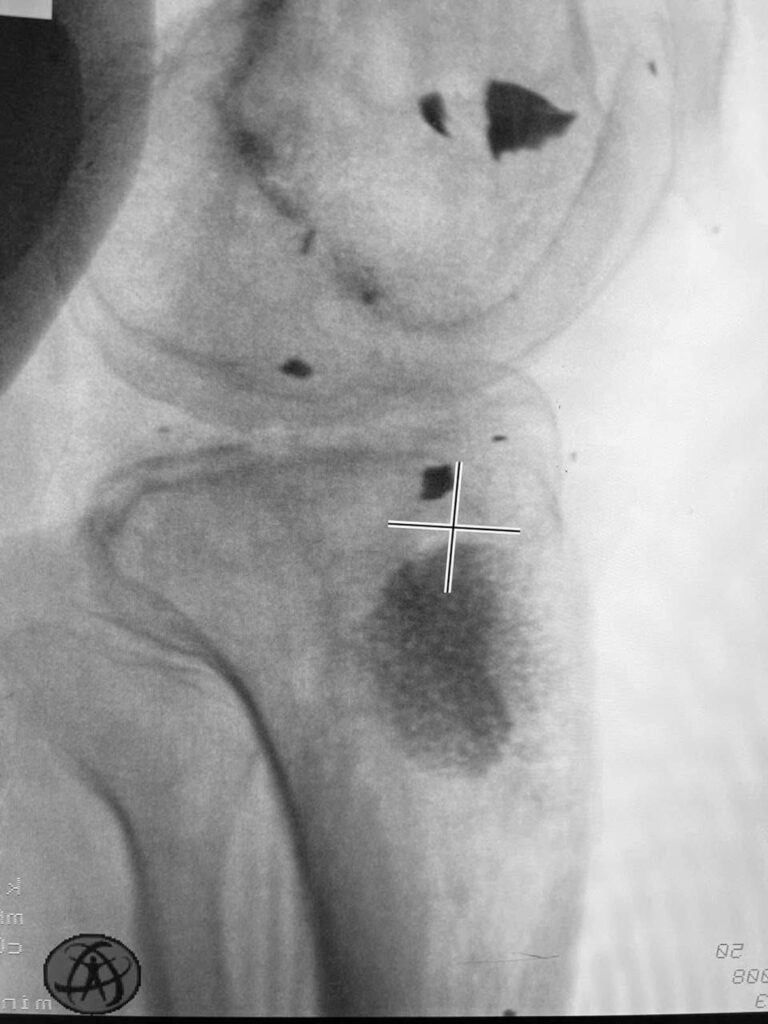

Тут вы видите рентгенограммы двух пациентов. В одном случае ранение голени у коленного сустава. В другом случае у сустава голеностопного с переломом костей. Поэтому там пластина еще стоит.

Обоим раненым (а каждый из них лечится по полгода уже) проведены по несколько операций дебридмента («чистка» кости и мягких тканей). К сожалению, это не остановило инфекцию.

В общем, все чаще и чаще приходится травматологам в Украине применять Bonalive. Это заменитель кости с антибактериальным действием. Только вот действует этот заменитель (финского производства) не за счет антибиотиков. Их в нем нет. А за счет того, что резко меняет Ph среды в кислую сторону. Бактерии погибают, привыкания к этому заменителю нет и быть не может (пока и если не появится какой-то новый, доселе неизвестный микроб), рост же собственной кости резко стимулируется.

Bonalive, как и всякий современный препарат высокотехнологичного производства, очень и очень дорог. Вот такой шприц-контейнер, как на фото, с 10 «кубиками» препарата стоит 500 евро (плюс-минус несколько процентов в зависимости от величины поставки).

Эти двое пациентов, чьи рентгенограммы вы видите, были прооперированы Председателем нашей Ассоциации AO Trauma Ukraine Олександром Рихтером в одном из военных госпиталей на западе Украины. Все зажило отлично.

Для первого раненого хватило 10 кубических сантиметров Bonalive, на второго – там, где пластина, ушло 20 «кубиков». Итого, в дополнение ко всему прочему – это 1500 евро.